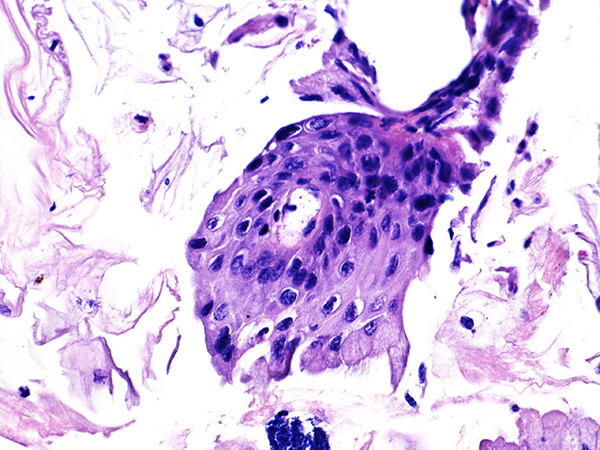

![]() Case 2

Soft Bx CIN 2

40x - High Power